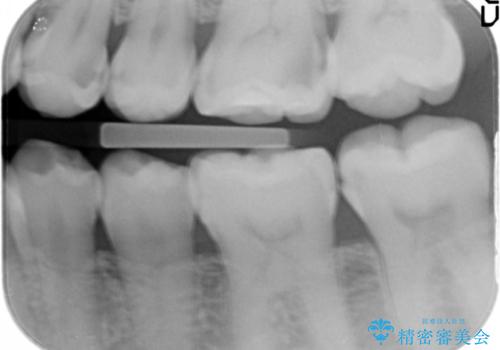

左下の奥歯2本にプラスチックの詰め物がされており、一見虫歯には見えない状態でした。

レントゲンを撮影したところ、奥歯の歯の間が虫歯が発見できました。